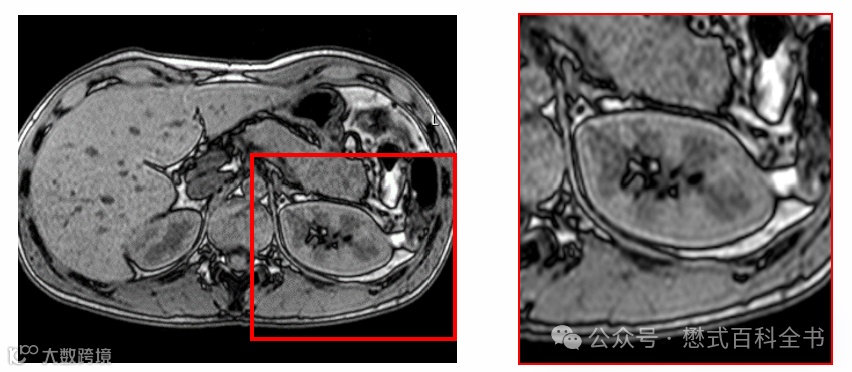

图10:T2-FLAIR中TI设置不合理导致脑脊液勾边

前文链接:磁共振参数的故事(二十九)——如何优化T2-FLAIR

讲到这里,大家理解了反弹点伪影的原理。出现这个伪影,主要和TI设置(刚好在一个体素内两种组织的反弹点)有关。

实际上只要是IR相关序列,采用模图重建,都可能产生反弹点伪影。

常见的IR序列模图重建的有:T2-FLAIR、T1-IR、STIR、MP-RAGE等。